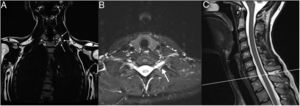

We conducted basic and needle-EMG examinations and found a severe inferior brachial plexopathy associated with severe chronic neurogenic impairment in the C8 and T1 innervated muscles. Further examination with magnetic resonance imaging (MRI) excluded any discoradicular conflict at the level of C8 and T1 but identified small excess of fat and edema in the form of a “teardrop” surrounding C8 and T1 suggesting compression of these nerves at the thoracic outlet level (Fig. 2). A standard radiography of the cervical spine clearly showed an abnormally elongated left C7 transverse process (Fig. 3). A diagnosis of TN-TOS was concluded.

Coronal (A), axial (B) and sagittal (C) MRI of the cervical spine. The coronal recordings are Dixon sequences where fat is emphasized (A), the axial and sagittal recordings are Dixon sequences where water is emphasized (B, C). (A) Notice more fat in the form of a “teardrop” (white on this image) around the left C8 under the transverse process (arrows), compared to right. (B, C) Hyperintensity around left nerve C8 (arrow), indicating more edema than on the right.